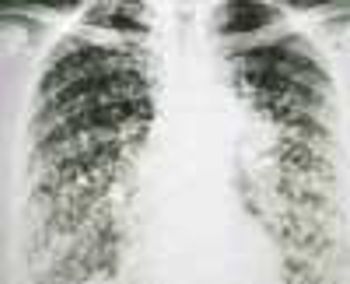

A 52-year-old woman (a nonsmoker) was hospitalized after experiencing a low-grade fever and dyspnea for a month. No abnormalities were noted on physical examination, but the chest film showed multiple nodules, both well- and ill-defined. Lung biopsy confirmed the diagnosis of bronchoalveolar carcinoma.